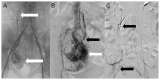

Uterine intravenous leiomyomatosis is an uncommon tumor, usually arising from the uterus, with nodular masses which extend intravascularly over variable distances and may reach the inferior vena cava, right atrium, and pulmonary arteries. Early diagnosis and surgical intervention are crucial as intracardiac leiomyomatosis not only causes cardiac symptoms but may result in pulmonary embolism and sudden death. Complete tumor resection is key in disease management, thus rendering cardiac-extending uterine intravenous leiomyomatosis one of the most challenging conditions for surgical treatment. The use of interventional radiology procedures can facilitate the surgical approach. We report the case of a massive pelvic recurrence of uterine leiomyomatosis with intracardiac extension and pulmonary embolism, analyzing management and surgical outcomes, highlighting the role of interventional radiology during the therapeutic pathway. Nonetheless, there are currently very few data available concerning the use of interventional radiology procedures in the therapeutic strategy of uterine intravenous leiomyomatosis with intracardiac extension.